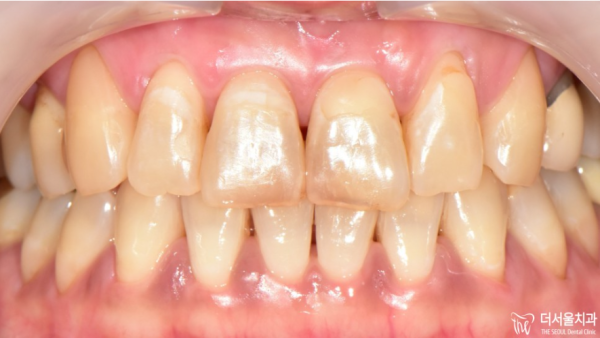

이 환자분께서는 치아가 거뭇거뭇해져서

타인들과 대화를 할때 신경이쓰셔 저희 치과를 찾아주셨는데요.

치아를 보면 곳곳에 짙은색의 치아우식(충치)가 보입니다.

This patient has darkened teeth

He visited our dentist because he was worried about talking to others.

If you look at the teeth, you can see dark teeth everywhere.

이 환자분의 충치치료와 치경부 마모증을 치료한 후의 모습입니다.

거뭇거뭇하게 우식이 있던 부분을 깔끔하게 치료한 것을 확인할 수 있고

치경부도 보기 좋게 잘 마무리가 되었죠?!

This is after treating this patient's tooth decay and dental abrasion.

You can see that the part where there was Woo-sik was treated neatly

It's done well for the dental carvings, right?